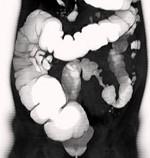

问题 女,56岁,腹胀、腹痛、左下腹包块三月余,无肛门排气,影像检查如图,最可能的诊断是 ( )

选项 A.乙状结肠Crohn病 B.乙状结肠结核 C.乙状结肠腺癌 D.乙状结肠淋巴瘤 E.乙状结肠息肉

答案 C